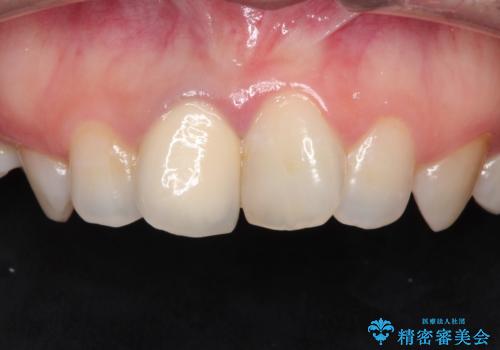

前歯の治療。再根管治療~セラミッククラウン

- 前歯の痛みを主訴に来院された患者様です。

再根管治療を行い、セラミックにて被せものを行いました。

症状も改善され満足して頂きました。